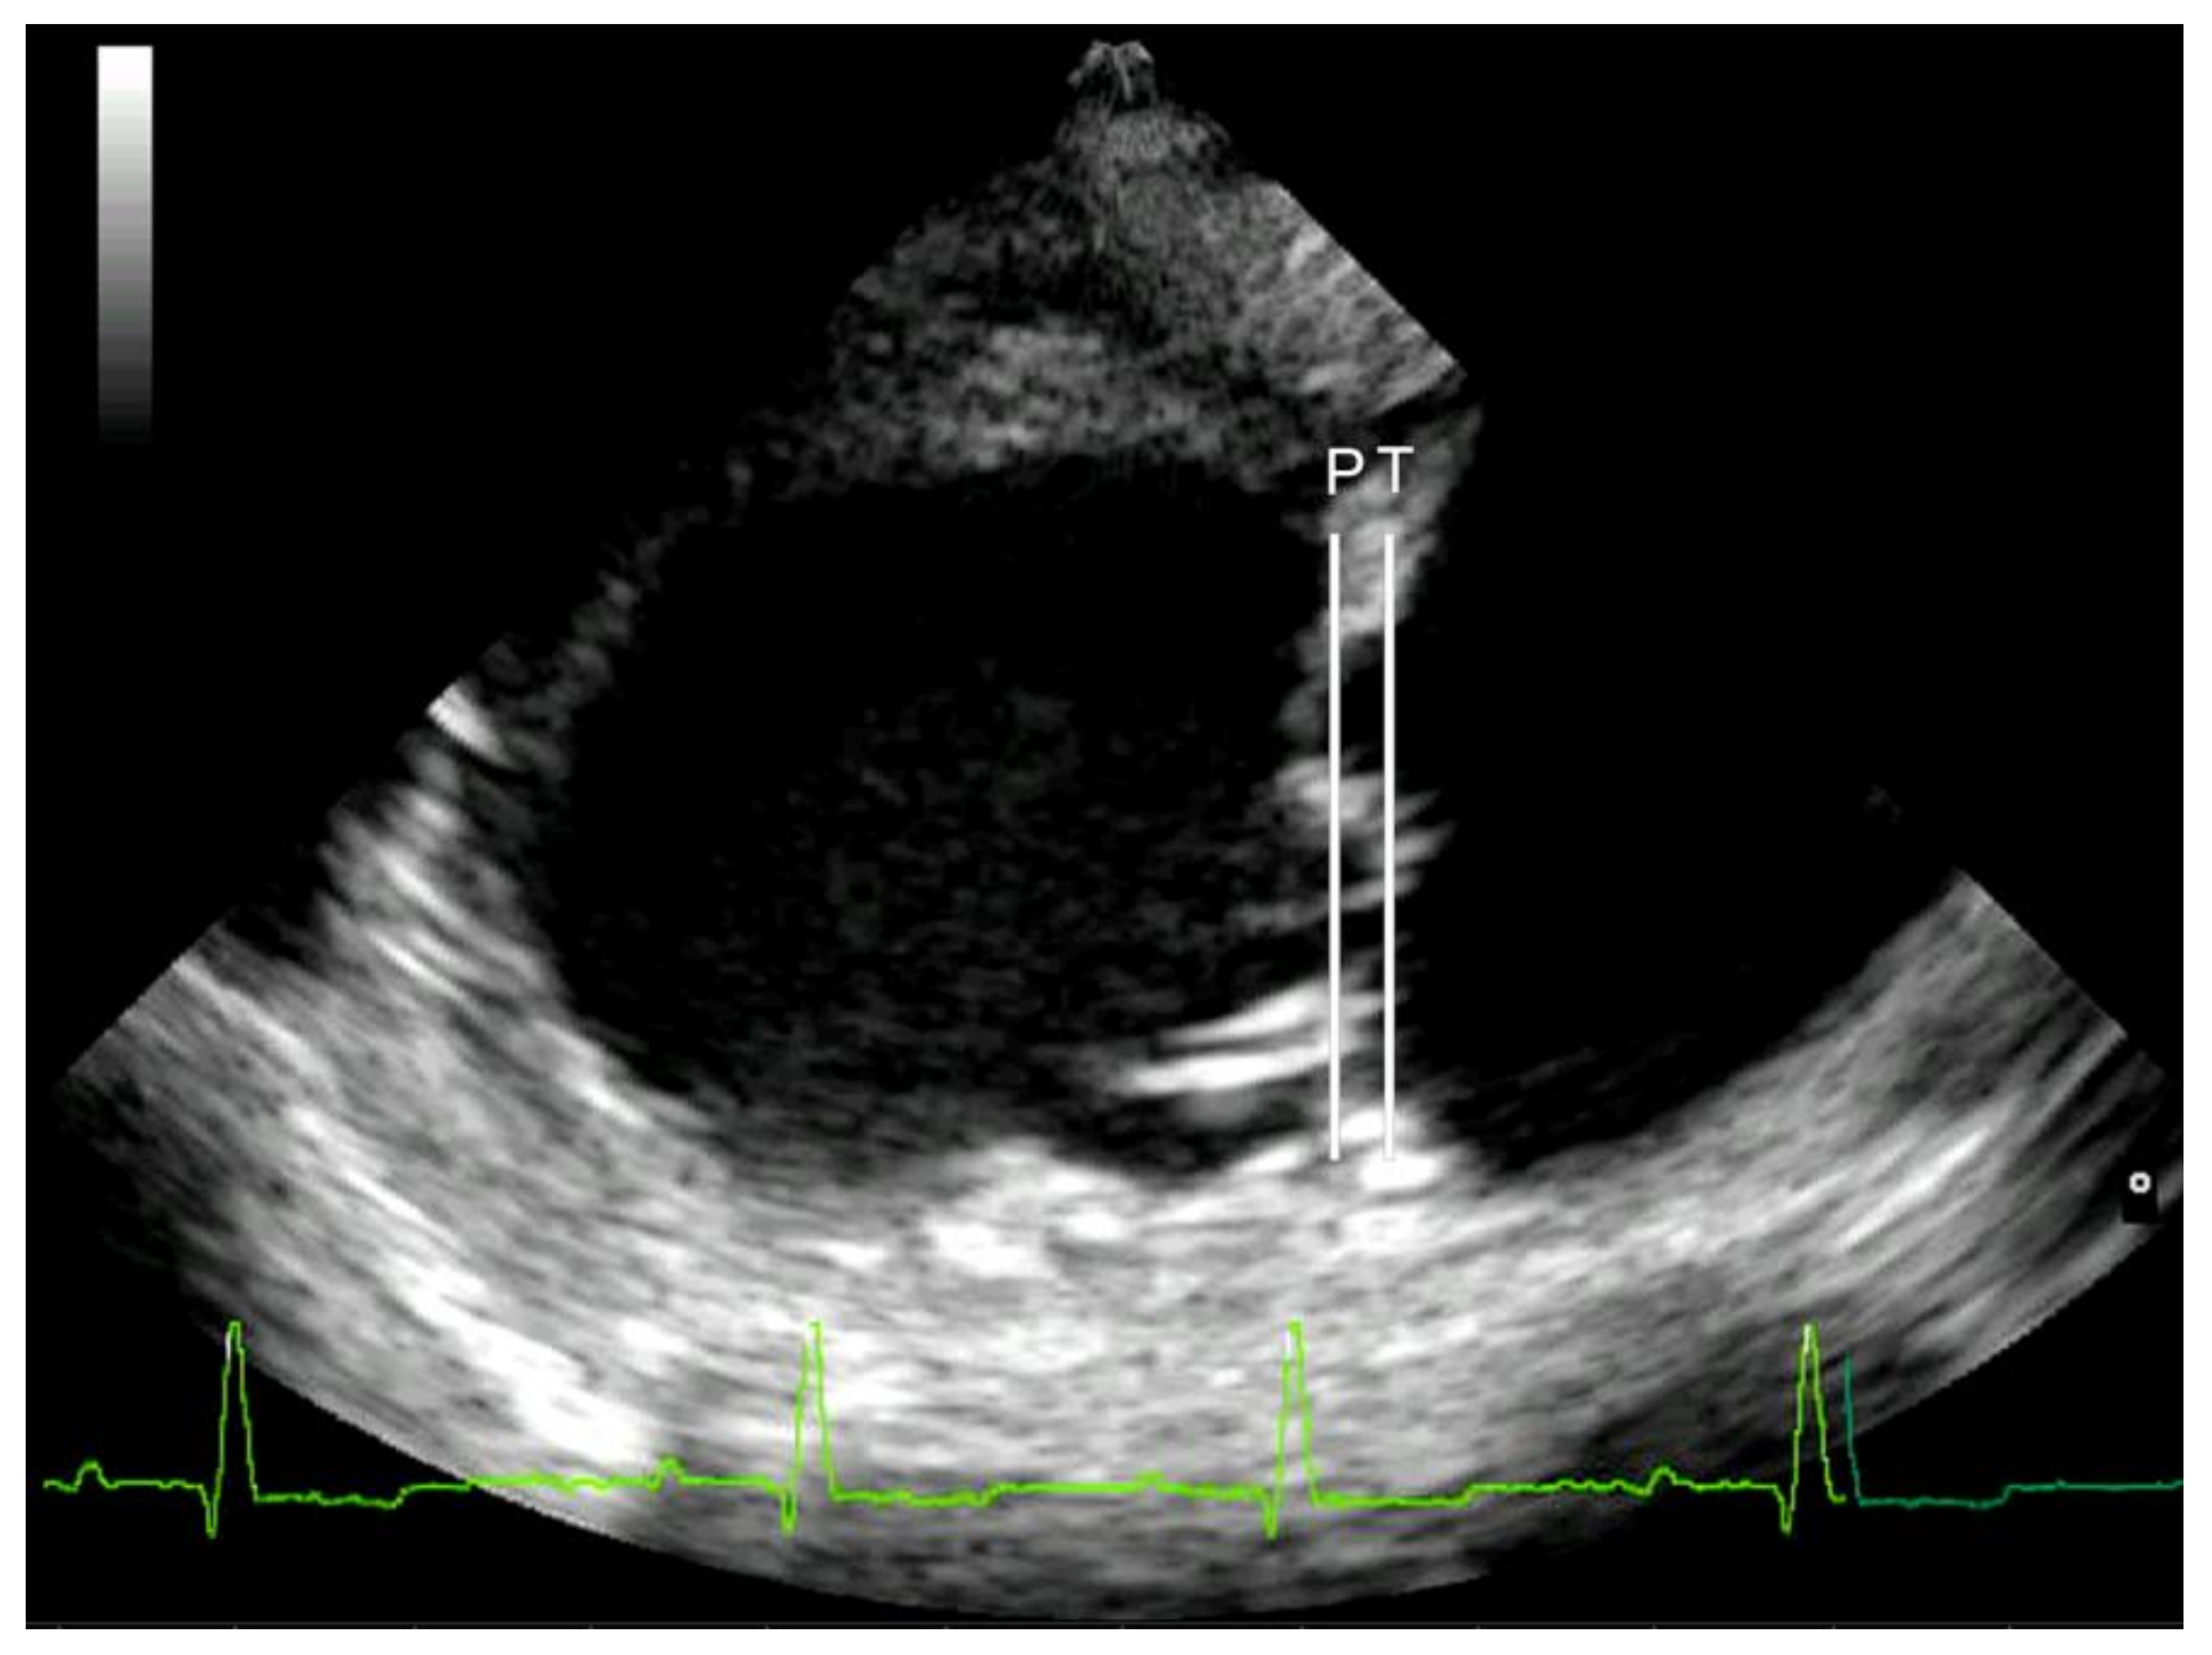

Mitral valve prolapse was considered mild if the leaflets were prolapsing but did not cross the line joining their pivotal points (line P), moderate if they protruded between the P line and the line joining half of the echoic areas located in the lower part of the atrial septum at the level of atrioventricular junction (T line), and severe if the leaflets exceeded the T line [29] (Figure 1). Lastly, MR was assessed by color Doppler, calculating the maximal ratio of the regurgitant jet area signal (ARJ) to the left atrium area (LAA) (ARJ/LAA ratio) in left parasternal long-axis view [24].

Figure 1. Right parasternal long-axis four-chamber view of a Cavalier King Charles Spaniel (CKCS) affected by myxomatous mitral valve disease (MMVD) in American College of Veterinary Internal Medicine (ACVIM) class D; severe mitral valve prolapse was assessed by the protrusion of one or both leaflets over line T. The arrows outline the severity of mitral valve prolapse and the affected leaflet. Line P is drawn from the hinge point of the anterior leaflet to the hinge point of the posterior leaflet. Line T is drawn from the middle of the elliptical echogenic area at the lower part of the atrial septum to the atrioventricular junction, i.e., the junction between the left ventricular wall/annulus fibrosis and the left atrial wall.